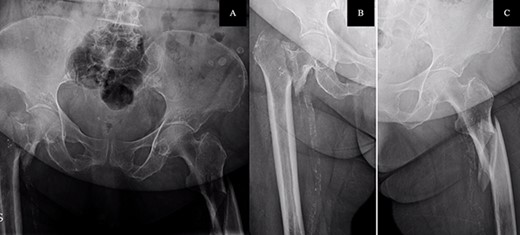

On examination, external rotation deformity of both lower limbs was evident, as well as pain upon palpation in the trochanteric region and during mobilization. The radiological study revealed a left and a right intertrochanteric femur fracture (Fig. 1). She was given analgesia, immobilized with two cutaneous tractions (Fig. 2), and was admitted to the Orthogeriatric Unit.

A. Anteroposterior pelvis radiograph evidencing a left subtrochanteric (AO:32-B2a) and a right intertrochanteric femur fracture (AO:31-A2.3). B. Radiograph of the right hip without any criteria of fracture instability. C. Radiograph of the left hip showing a simple wedge pattern of fracture.